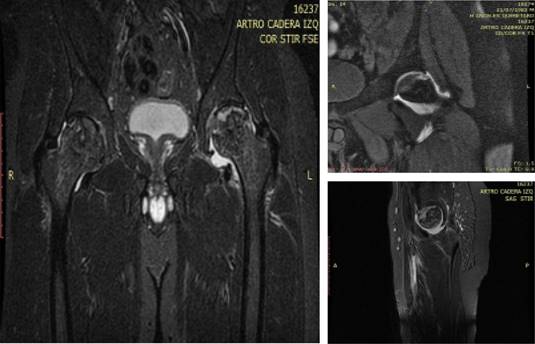

A la exploración física dirigida, encontramos marcha claudicante a expensas de extremidad inferior izquierda; arcos de movilidad de cadera izquierda: flexión de 45o, abducción de 30o, extensión de 20o, rotación externa e interna de 15o. Se solicita radiografía anteroposterior de pelvis como estudio inicial, donde se observa pérdida de la esfericidad de la cabeza femoral izquierda, así como geodas e imagen esclerótica en forma de semiluna. Se procede a realizar artrorresonancia magnética, la cual evidencia colapso de la cabeza femoral izquierda, ambas caderas con zonas de hiperintensidad difusas e imagen en semiluna en cadera izquierda (Figura 1).

Figura 1: Artrorresonancia magnética de cadera. Se observa imagen en semiluna a nivel de la cadera izquierda, colapso, geodas y pérdida de la esfericidad normal.